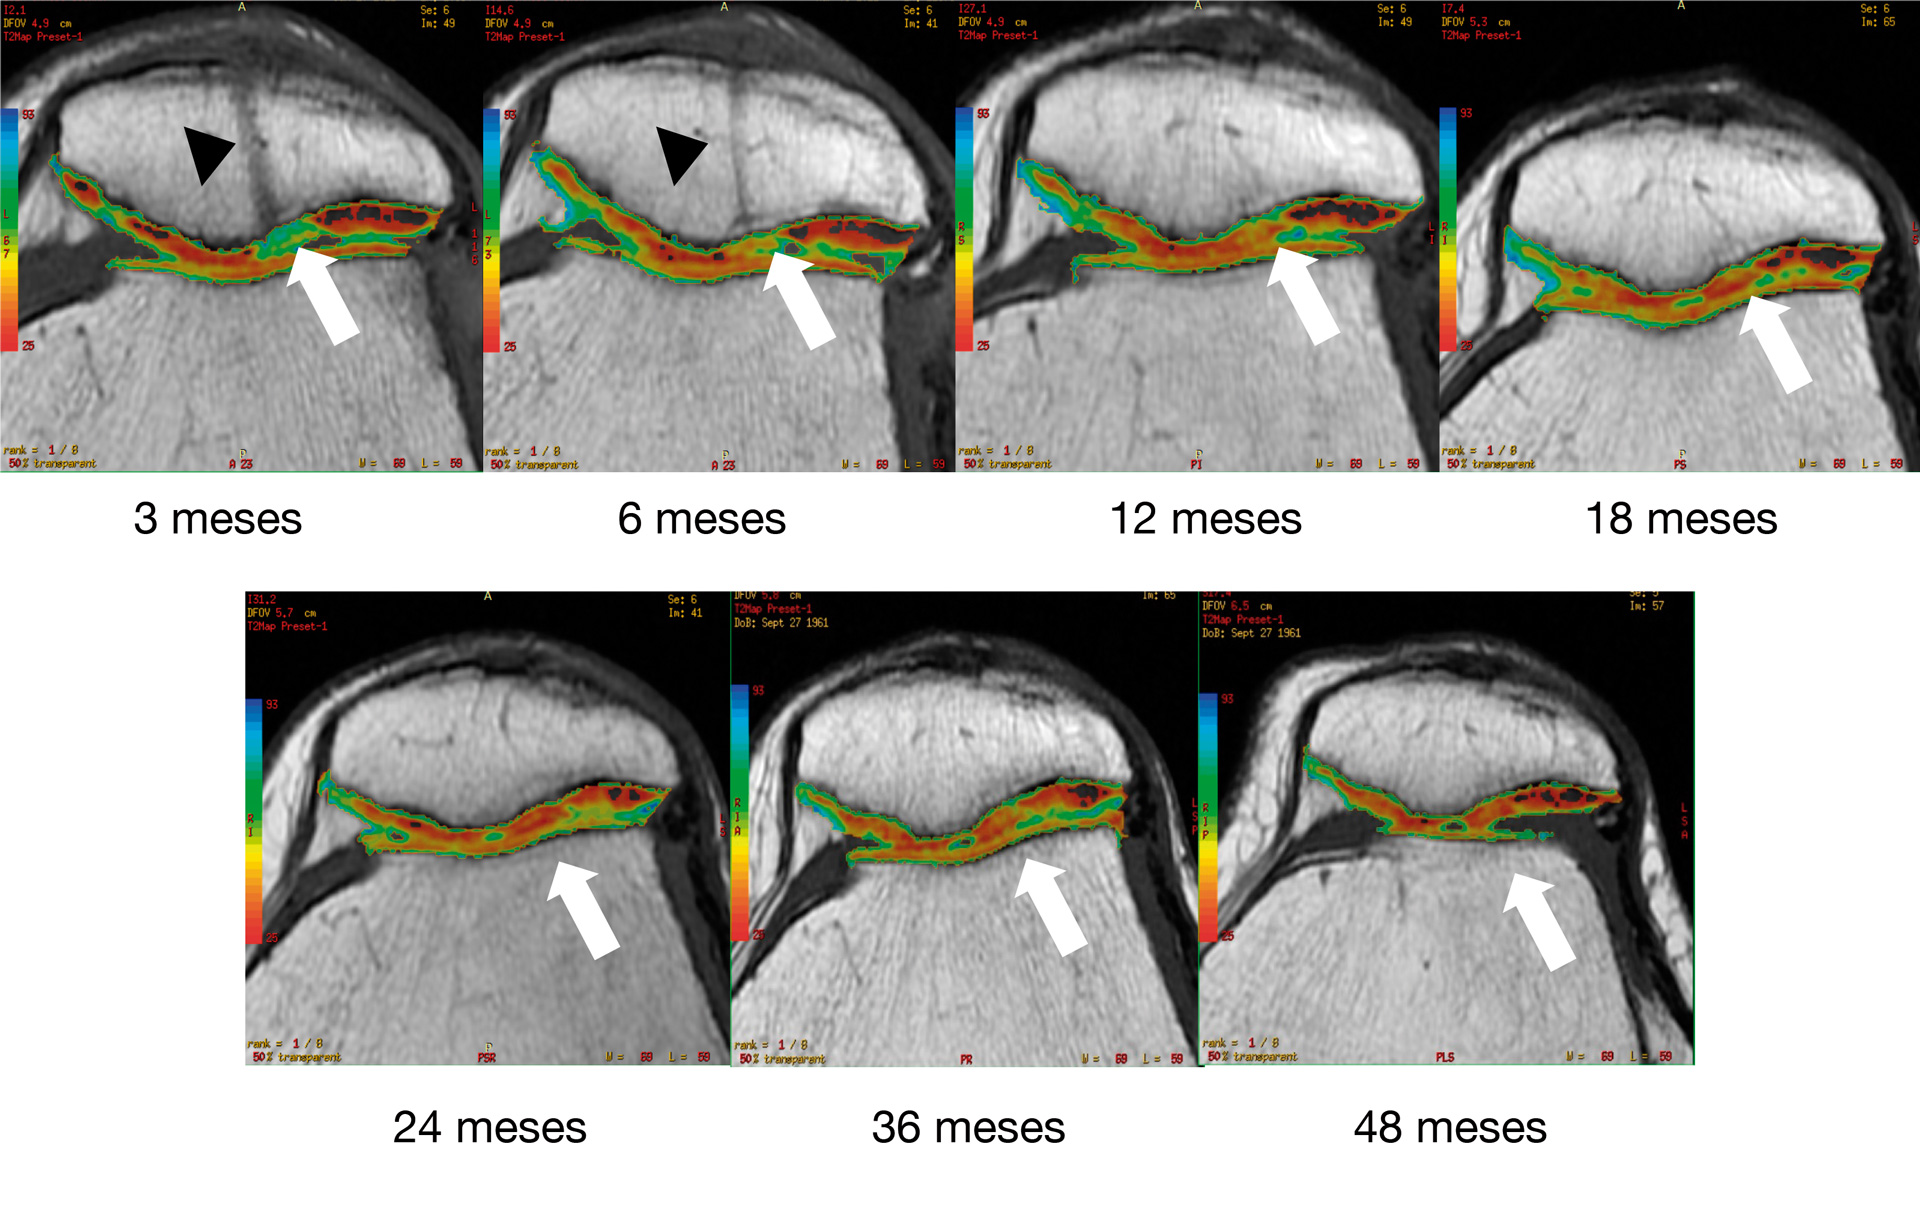

Los cambios morfológicos subjetivos se aprecian a partir de los 12 meses: en la escala se asignó al color azul al valor de 95 ms y al rojo al valor de 25 ms; la coloración tiene una tendencia al verde-azul y progresivamente cambia al rojo-naranja, que es la que muestra el cartílago nativo. En la Figura 7 se aprecia un ejemplo del seguimiento por mapeo en T2. Al comparar el implante con el tejido nativo se aprecia cómo a partir de los 12 meses se parece al cartílago nativo.

Figura 7. Seguimiento cualitativo subjetivo por mapeo T2. Las flechas blancas indican la zona del implante: obsérvese el cambio progresivo de la ausencia de tejido y la posterior formación de tejido con características morfológicas similares a las del tejido nativo adyacente. Las puntas de flecha negras indican una figura correspondiente a un túnel transpatelar el cual a los 12 meses de postoperado desaparece completamente.